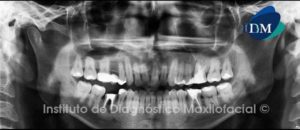

Paciente sexo femenino, 11 años de edad, acude a la consulta para evaluación previo a tratamiento odontológico. Al examen radiográfico panorámico (Fig. 1) observamos múltiples lesiones radiolúcidas que comprometen ambos maxilares.